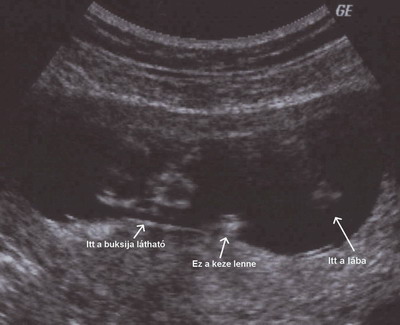

Kissvirág, még ha azt is mondod, h nem olyan jó a kép nekem nagyon tetszik, és azért csak óvatosan azzal a pakolással.